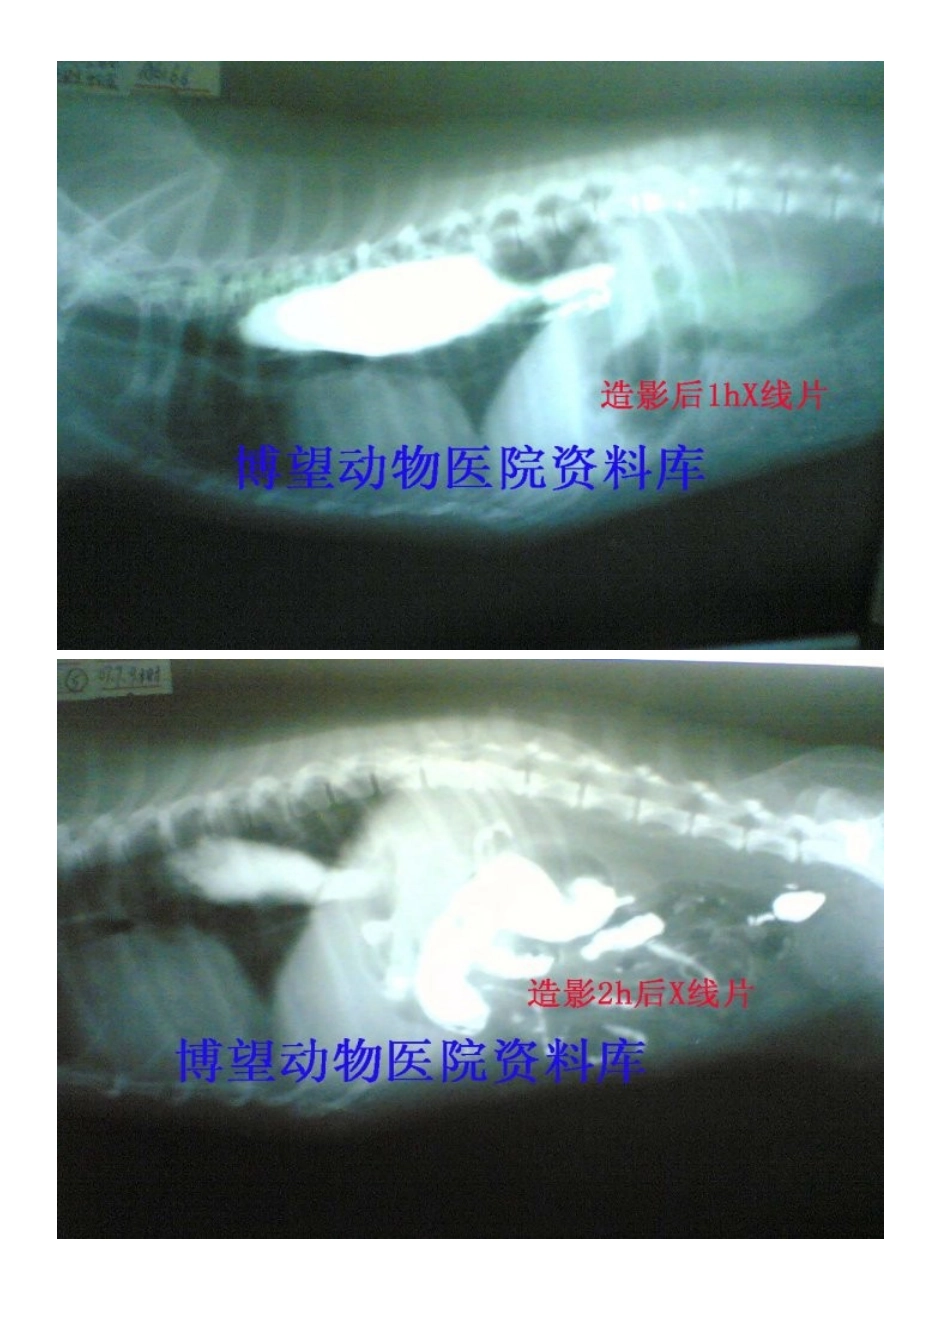

病例5——保守——成年犬巨食道症---X片VIP免费

一、定义1,成年动物发生的整食管扩张且蠕动停止.2,成年原发性巨食管症是指不明原因的食管扩张.3,成年后天性巨食管症是指原因明了的食管扩张.4,成年巨食管症在犬常引起逆流而在猫少见.二、病因1,许多病例的病因不清,从而导致先天性的类别.2,许多病理情况都能引起食管扩张或与之有关.3,后天性(继发)病因包括神经肌肉性疾病,免疫调节紊乱,激素失衡,中毒及炎症.三、临床症状1,发生食物和液体返流,但在进食后发生返流的时段有很大差异.2,吞咽痛在炎症和过度扩张时可见,表现出唾液分泌过多,反复吞咽和颈部姿势异常.3,伴随食物发酵而出现口臭.4,当发生异物性肺炎时出现呼吸紧迫(湿咳,啰音,呼吸困难).5,营养不良会导致严重的恶病质或虚弱.6,与继发病因有关的症状将可看到:A,肌肉痛和多肌炎性僵步.B,神经肌肉病性虚弱.C,中毒或阿狄森病(肾上腺皮质机能减退)引起的胃肠症状.四、诊断1,准确了解病史很重要.A,呕吐和返流混淆易产生误诊.B,成年动物,尤其是犬有返流病史者怀疑巨食管症.2,体检可能提供继发性巨食管症病因的线索.A,注意肌肉痛,虚弱,神经性缺损和精神状态的变化.B,在肾上腺皮质机能紊乱时可见到皮肤异常.3,X光照相是合适的.A,颈胸部一般放射检查即可发现食管内存留气体、液体和食物积留.B,异物性肺炎时可见肺泡浊斑.C,食管部钡餐造影可显示其扩张及其他结构异常(.D,荧光镜透视(若适宜)可获得巨食管迟缓的有用资料.4,实验室诊断很有益.A,最基本的实验室检查包括全血细胞计数,全面的生化指标检测和尿液分析.B,肌激酶分析可判断肌肉病或肌炎,而测定血清胆固醇可诊断皮质激素功能紊乱.C,所有怀疑肌无力而巨食管症不确切的病例均应作乙酰胆碱受体滴度测定.D,临床可疑病例可作传统实验室检查.5,巨食管症诊断一般无须作食管镜检查,除非怀疑有肿瘤或其他结构异常.五、治疗1,患有后天性巨食管症的动物随时都可针对引起食管扩张的因素进行治疗,多数会改善机关机能.2,先天性巨食管症及药物治疗无效的后天性巨食管症可进行对症治疗.A,抬高饲槽位置有利于食物通过而入胃.B,通常饲喂少量满足体能需要即可.C,改变食物硬度(流汁与大丸料比较)看最能耐受哪种日粮.一般固体颗粒料会更好的刺激食管蠕动收缩.D,患有严重吸入性肺炎的动物需特别注意.3,作胃造影术后以造管投喂既可保证营养供应,可减少误吸的危险.4,可广谱抗菌药治疗细菌感染.5,机能促进药效果尚未证实.A,西沙比利(促进剂)0.5mg/kg,PO,BID可改善猫的食管功能底下.B,有报道证实可能改善某些犬的巨食管症临床症状.六、监护1,每隔1~2个月复查以监测病情发展.2,复查胸片以证实食管扩张的异物性肺炎.3,成年巨食管症一般预后不良.A,原发病的动物往往死亡或因病而施行安乐死.B,获得性疾病的动物药物治疗可能有效.C,犬由于严重肌无力引起的巨食管症预后良好.用支持疗法半个疗程即可奏效.